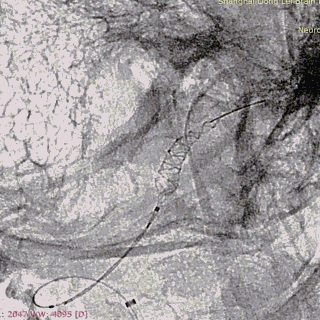

第一枚2*20支架通过017支架微导管到位。

支架远端打开。

支架远端打开情况。

支架中段打开,过50%释放标记点。

造影显示支架整体打开良好。

支架完全释放。

微导管沿推送杆通过支架,撤出推送杆,保留通路。

造影显示支架打开良好,准备桥接第二枚支架。

第二枚3*25支架沿017支架微导管上高。

第二枚支架远端释放。

第二枚支架释放至中段。

中段释放适当推挤系统,保持贴壁良好。

中段释放后造影。

继续释放支架。

继续释放支架,造影观察贴壁良好。

完全释放支架。

支架微导管沿推送导丝上高并将推送导丝撤出。

术后即刻造影。